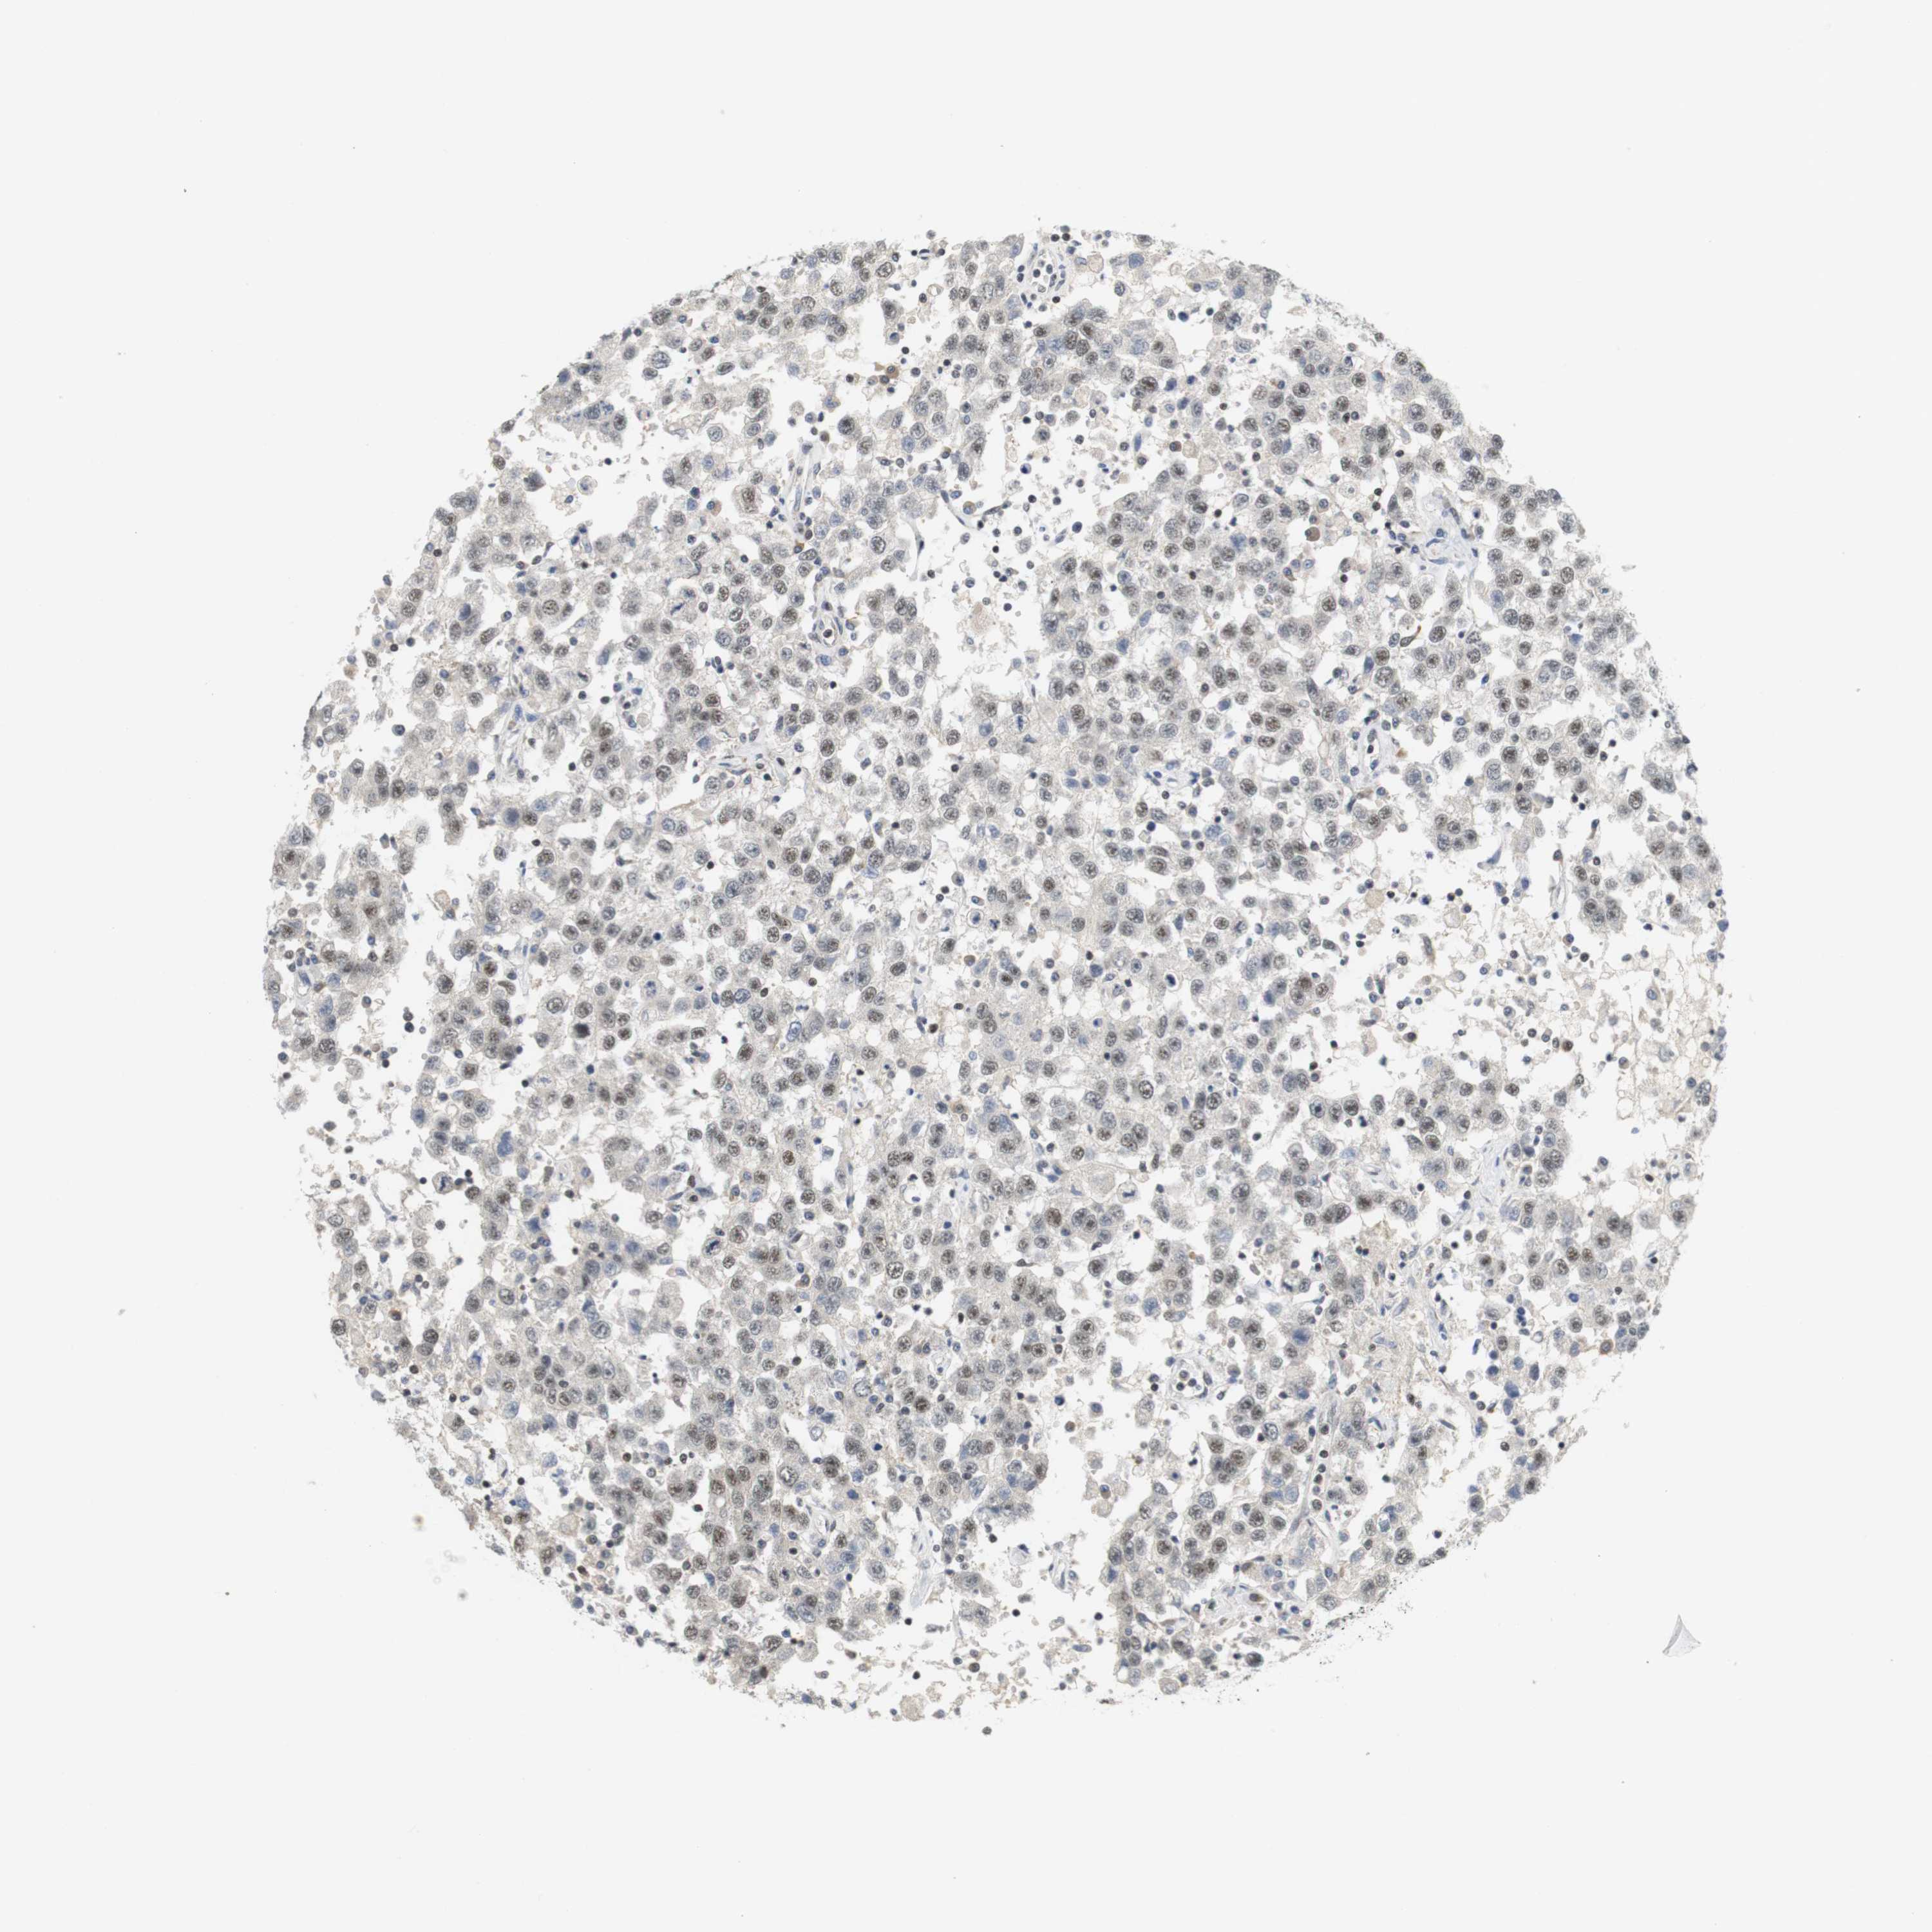

TESTIS CANCER - Protein expressioni

A mouse-over function shows sample information and annotation data. Click on an image to view it in a full screen mode. Samples can be filtered based on level of antibody staining by selecting one or several of the following categories: high, medium, low and not detected. The assay and annotation is described here.

Note that samples used for immunohistochemistry by the Human Protein Atlas do not correspond to samples in the TCGA dataset.

Antibody stainingi

Antibody staining in the annotated cell types in the current human tissue is reported as not detected, low, medium, or high, based on conventional immunohistochemistry profiling in selected tissues. This score is based on the combination of the staining intensity and fraction of stained cells.

Each image is clickable and will lead to virtual microscopy that enables deeper exploration of all samples and also displays staining intensity scores, fraction scores and subcellular localization as well as patient and tissue information for each sample.

Antibody HPA015055

Staining

High

Medium

Low

Not detected

Intensity

Strong

Moderate

Weak

Negative

Quantity

>75%

75%-25%

<25%

None

Location

Nuclear

Cytoplasmic/membranous

Cytoplasmic/membranous,nuclear

Carcinoma, Embryonal, NOS

Seminoma, NOS

Teratoma, malignant, NOS